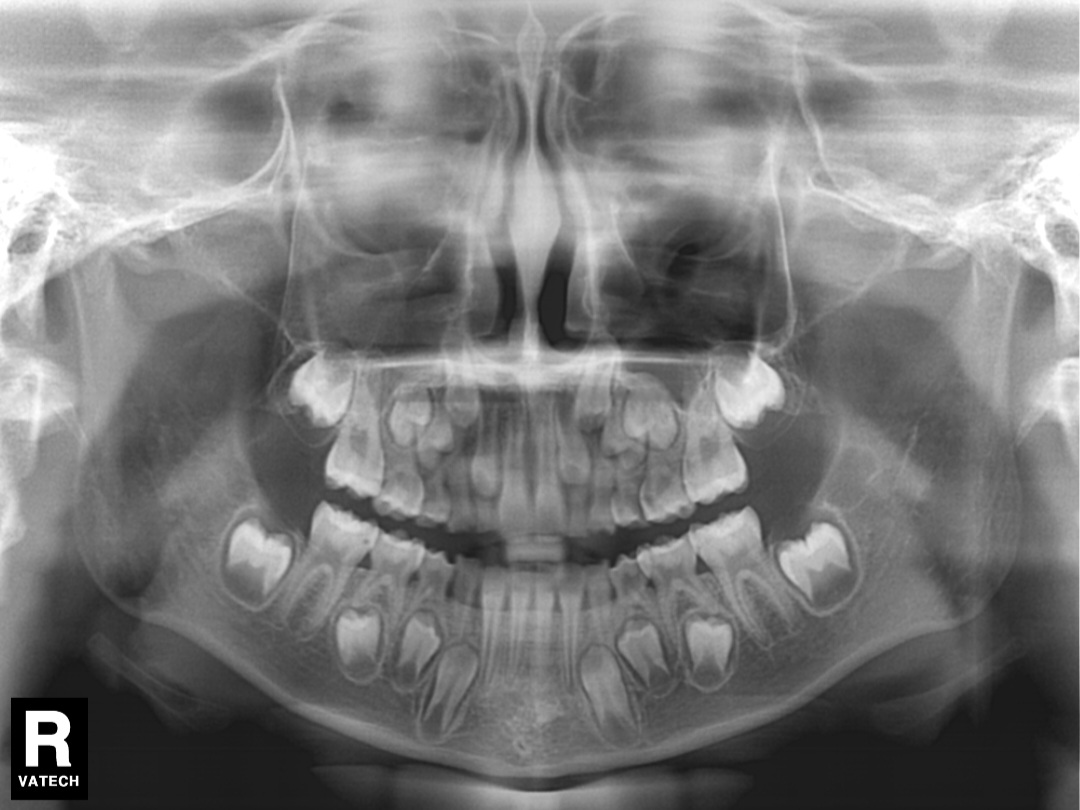

엄마인 제가 안일하게 치실을 안써서, 초등학교1학년(만7세8개월) 딸아이 어금니(영구치포함)에 모두 사이 충치가 생겼습니다. 선생님 책에도 치료가 필요하다고 하신 사이 충치입니다ㅠㅠㅠㅠㅠ

치과에 가보니 10개~13개정도 치료해야 한다고 합니다.(치료계획서 미호함된 오른쪽 아랫니도 포함 어금니전체)

영구치 빨리 치료해야 한다 하시고 영구치는 너무나 중요한데 썩었으니 약간씩 생긴 사이충치는 모두 떼우자고 하시고, 유치들은 신경치료 하고크라운으로 5개정도 하고, 나머지는 떼우자고 하시는데....

약간씩 생긴 영구치의 충치는 깨끗하게 치료하는데 맞는지,

육안으로 보이지도 않고 아프지도 않은 충치들 모두 제거 하는게 맞을까요?(육안으로 보이고, 과거 한참 아프다고 했고 현재는 안아프다고 하지만, 검은 구멍이 생기고 음식이 많이 끼는 불편한 곳은 왼쪽 윗니 뒤에서 두번째 사이입니다)

(영구치의 레진 치료가 필요한 상태인가요?

유치 중 신경치료가 필요한 이가 있을까요?)